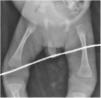

La analítica mostró: serología anti-Treponema pallidum reactiva por inmunoquimioluminiscencia (CMIA) (25,8S/CO), anemia (10g/dl), leucocitos (9,4×103/ml), trombocitopenia (95×103/ml), hipoglucemia (58mg/dl), transaminasemia (AST 554U/l, ALT 135U/l) con hiperbilirrubinemia directa (3,7mg/dl), hipoalbuminemia (1,3g/dl), radiografías con periostitis en huesos largos (fig. 3), carga viral de VIH no detectada. La punción lumbar reveló hipoglucorraquia (28mg/dl), hiperproteinorraquia (59mg/dl), sin pleocitosis y VDRL reactivo. Se reporta VDRL materno reactivo (1:64).